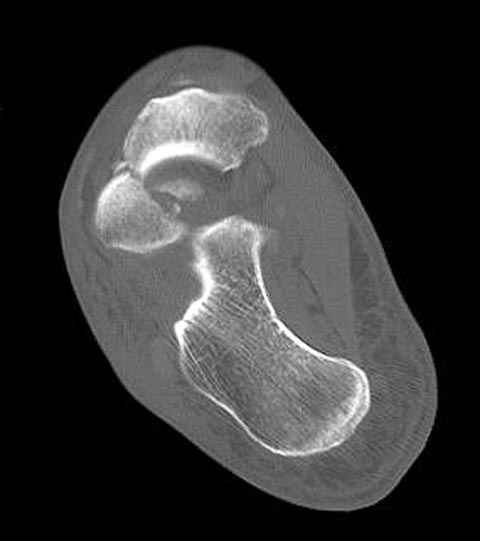

Уважаемые участники русского Ортофорума, поздравляю всех со всеми прошедшими праздниками: Новым годом, Рождеством, Hanukkah, Kwanzaa, желаю участникам всего наилучшего и здоровья.Повреждение таранной кости.Больной 81г автоавария, повреждение таранной кости, здесь снимки. Какие рекомендации?Djoldas Kuldjanov, MDDepartment of Orthopedic SurgerySt. Louis University Medical Center

Вдогонку по поводу перелома таранной кости, больная 81, не страдает диабетом, перелом закрытый, в первый же день поступления ограничились временным наружным фиксатором (как на снимке).

Из-за отека на стопе тактика лечения у всех была

одинаковая: временная наружная фиксация до спадения отека, при изолированных переломах они выписывались домой и через дней 7 госпитализировались на оперативное лечение.

Примеры на снимке...